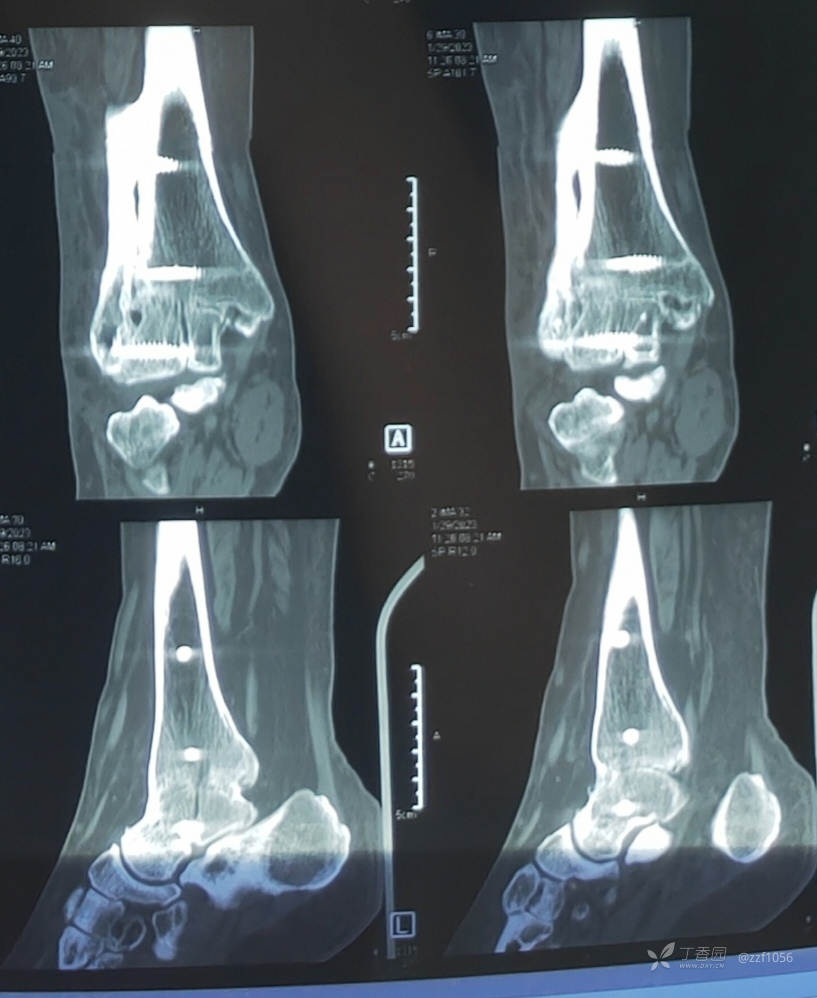

入院诊断:右踝关节骨折术后畸形融合,内固定存留

入院完善检查,拟定行右踝内固定取出、融合翻修术。

看一下目前CT